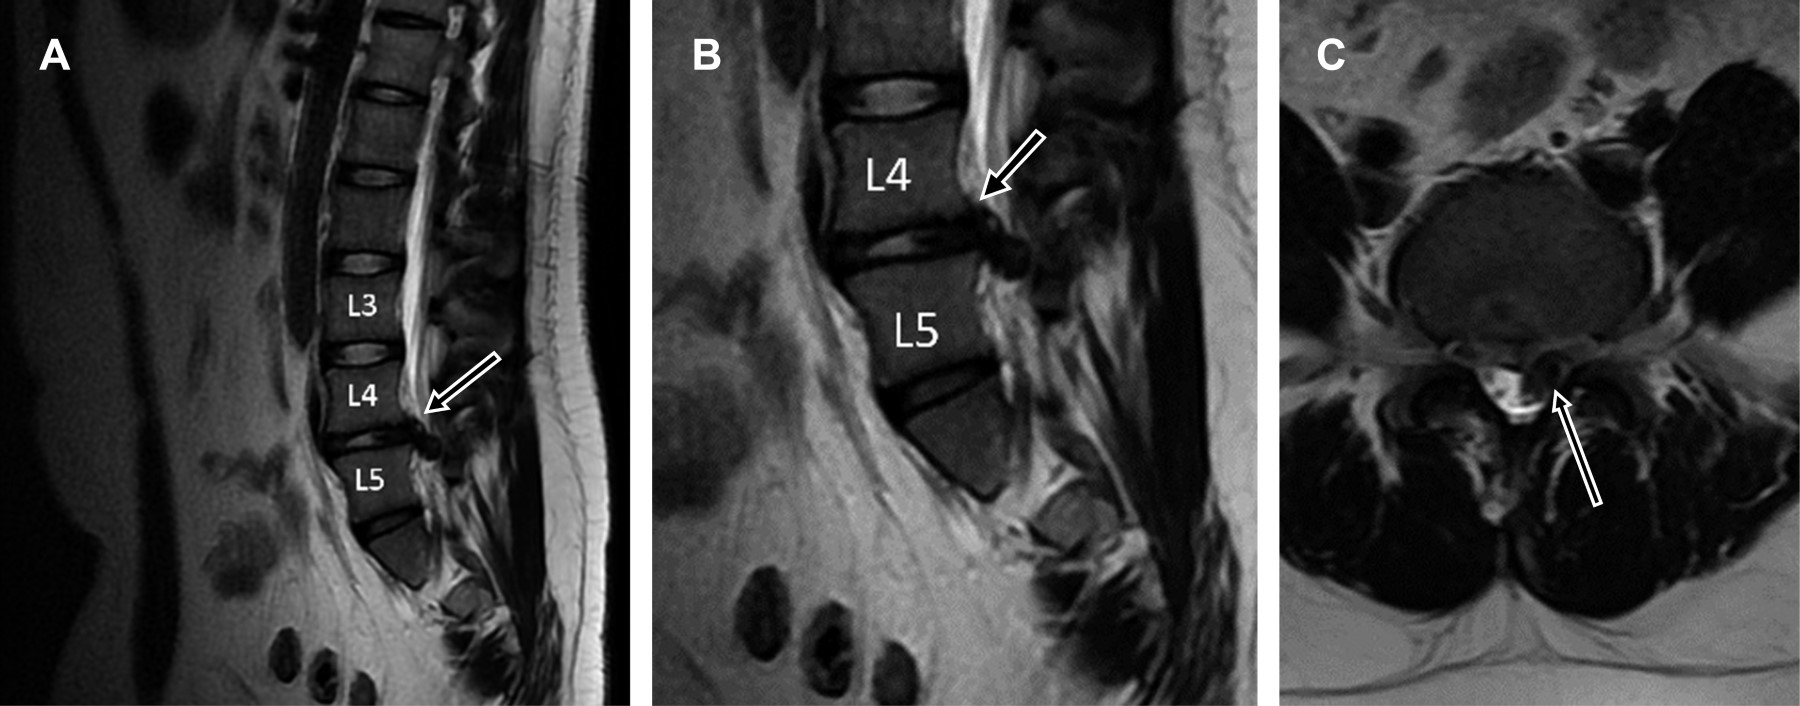

Masculino de 23 años sufrió accidente de tráfico, colisionando su motocicleta contra vehículo en movimiento, chocando contra el piso a 8 m del percance, presentando dolor lumbar severo; a la exploración se encontró: dolor severo a la palpación de región lumbar, exquisito a la percusión de apófisis espinosas L4 y L5, paresia 2/5 en músculos inervados por raíces L4, L5 y S1 izquierdos, disminución de reflejos rotuliano y aquíleo izquierdos, pulsos y llenado capilar normales con diagnóstico de posible fractura vertebral L4-L5 y compresión radicular L4-L5 S1. Se efectuó tomografía computarizada (Figura 1) y resonancia magnética de región lumbar (Figura 2), encontrando: fractura del borde posterior inferior de L4, con extrusión masiva de material discal L4/L5 de localización paracentral izquierda que obstruye agujero de conjunción. Se efectuó laminectomía y discoidectomía, y fue dado de alta hospitalaria. A 21 días de seguimiento, paciente asintomático con recuperación de fuerza muscular, sensibilidad y reflejos normales.

Figura 2